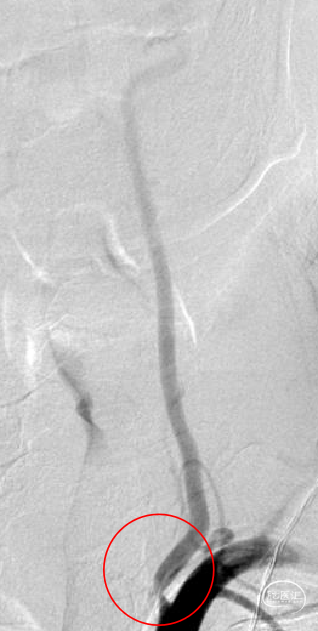

术前术后对比:

术前

术后

术前术后对比:

术前

术后